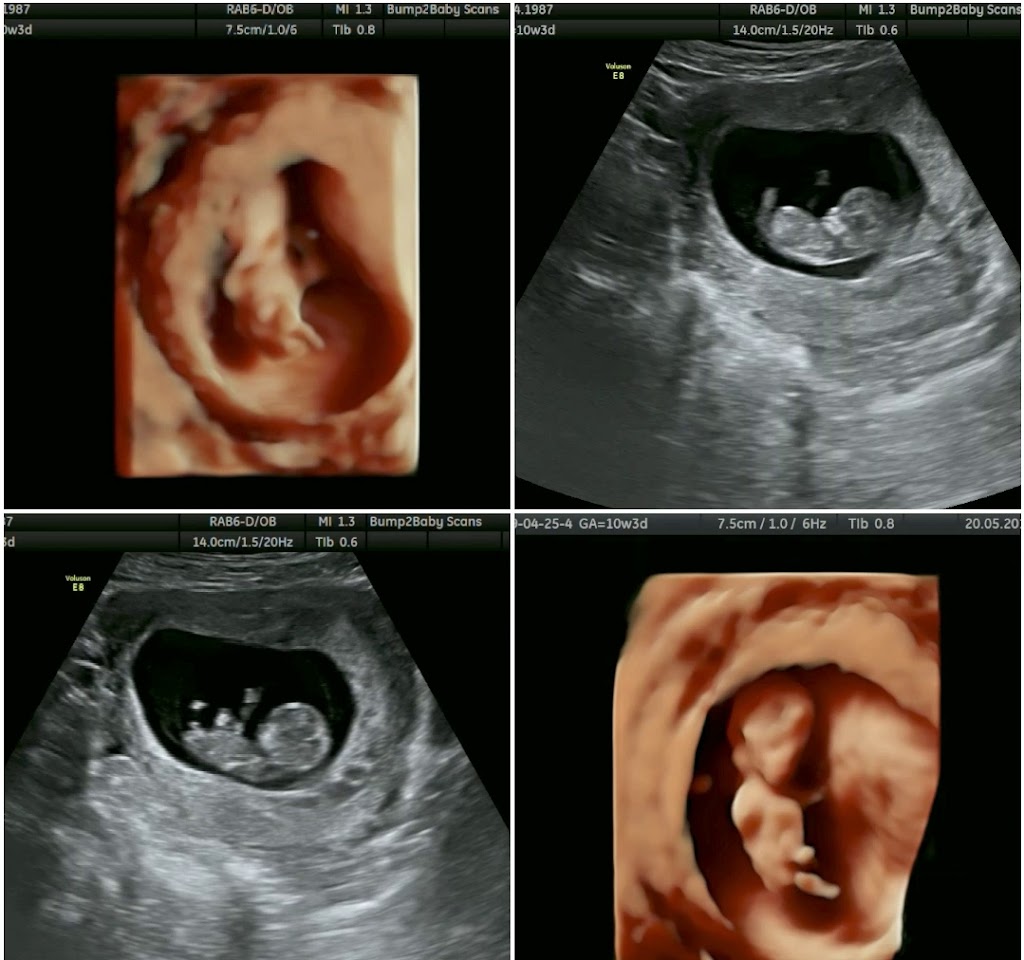

Bump2baby Scans

Bump2baby Scans offers a variety of ultrasound scans, including early pregnancy scans, gender scans, growth and wellbeing scans, and 4D scans. In addition, they provide a range of packages that cater to different stages of pregnancy, such as the Early Reassurance Package and the Ultimate 4D Experience. Customers can also purchase gift vouchers for loved ones.